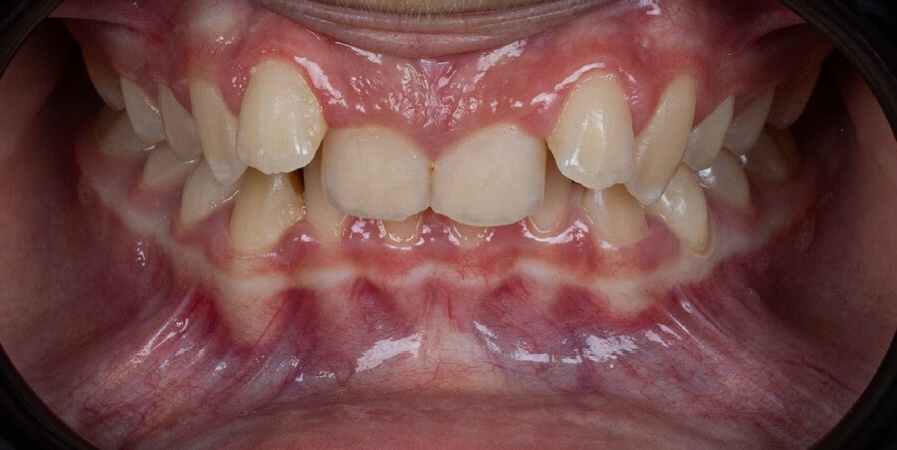

Un paciente de 13 años con maloclusión de clase II división 2 y mordida profunda fue tratado con el sistema de avance mandibular Angel Aligner A6. El protocolo combinó el avance mandibular, la expansión del arco, la intrusión de los incisivos y el refinamiento con elásticos de clase II, logrando una corrección funcional de la mordida y una mejora de la estética de la sonrisa en 10 meses.

Este caso, dirigido por la Dra. Romina Vignolo Lobato, muestra el tratamiento de una paciente de 12 años con una maloclusión de clase II. Utilizando el sistema Angel Aligner Pro con el protocolo A8 y un salto virtual asimétrico, el tratamiento logró resolver el apiñamiento, corregir la mordida y mejorar el perfil facial en solo 11 meses con 30 alineadores. El enfoque mínimamente invasivo combinó la eficiencia con un control preciso, lo que permitió obtener resultados tanto funcionales como estéticos.

Este caso muestra un enfoque innovador para corregir la retrusión del maxilar inferior en pacientes en crecimiento utilizando el Angel Aligner A6. El sistema combina el tratamiento ortopédico y ortodóncico en un único protocolo, permitiendo el avance simultáneo del maxilar inferior y la alineación de los dientes. Gracias a la planificación digital y a los alineadores estéticos, el tratamiento es eficaz y cómodo para el paciente. Este caso fue tratado por el Dr. Giacomo Scuzzo